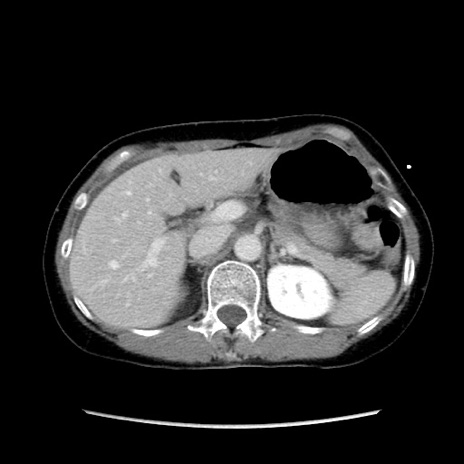

症例32(横断像)

【症例】40歳代 女性

【主訴】上腹部痛、嘔気・嘔吐

【現病歴】約9時間前頃から急に上腹部痛、嘔気、嘔吐が出現。改善しないため救急要請。

【既往歴】子宮頚癌(広汎子宮全摘術、放射線療法)、腸閉塞

【身体所見】腹部:平坦、軟、腸雑音亢進、上腹部を中心に腹部全体に圧痛あり。

【データ】WBC 8400、CRP 0.03